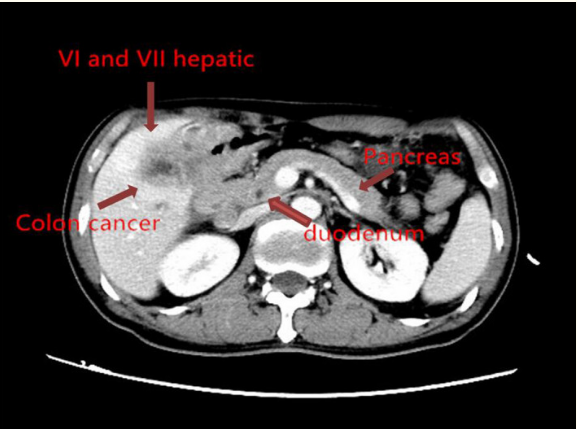

一名54岁的的男性患者,体重指数16.5,近两个月出现食欲不振以及体重降低,抽血检查发现癌胚抗原CEA7.77ng/mL,CA19-9水平为357.3U/ml,腹部CT提示结肠肝区肿瘤,侵袭肝脏VI段和VII段,胆囊,十二指肠,如图1所示;结肠镜检查发现结肠肝曲肿瘤占位,如图2所示。取活组织病理提示低分化管状腺癌。

图1 腹部CT提示结肠肝区肿瘤,侵袭肝脏VI段和VII段,胆囊,十二指肠